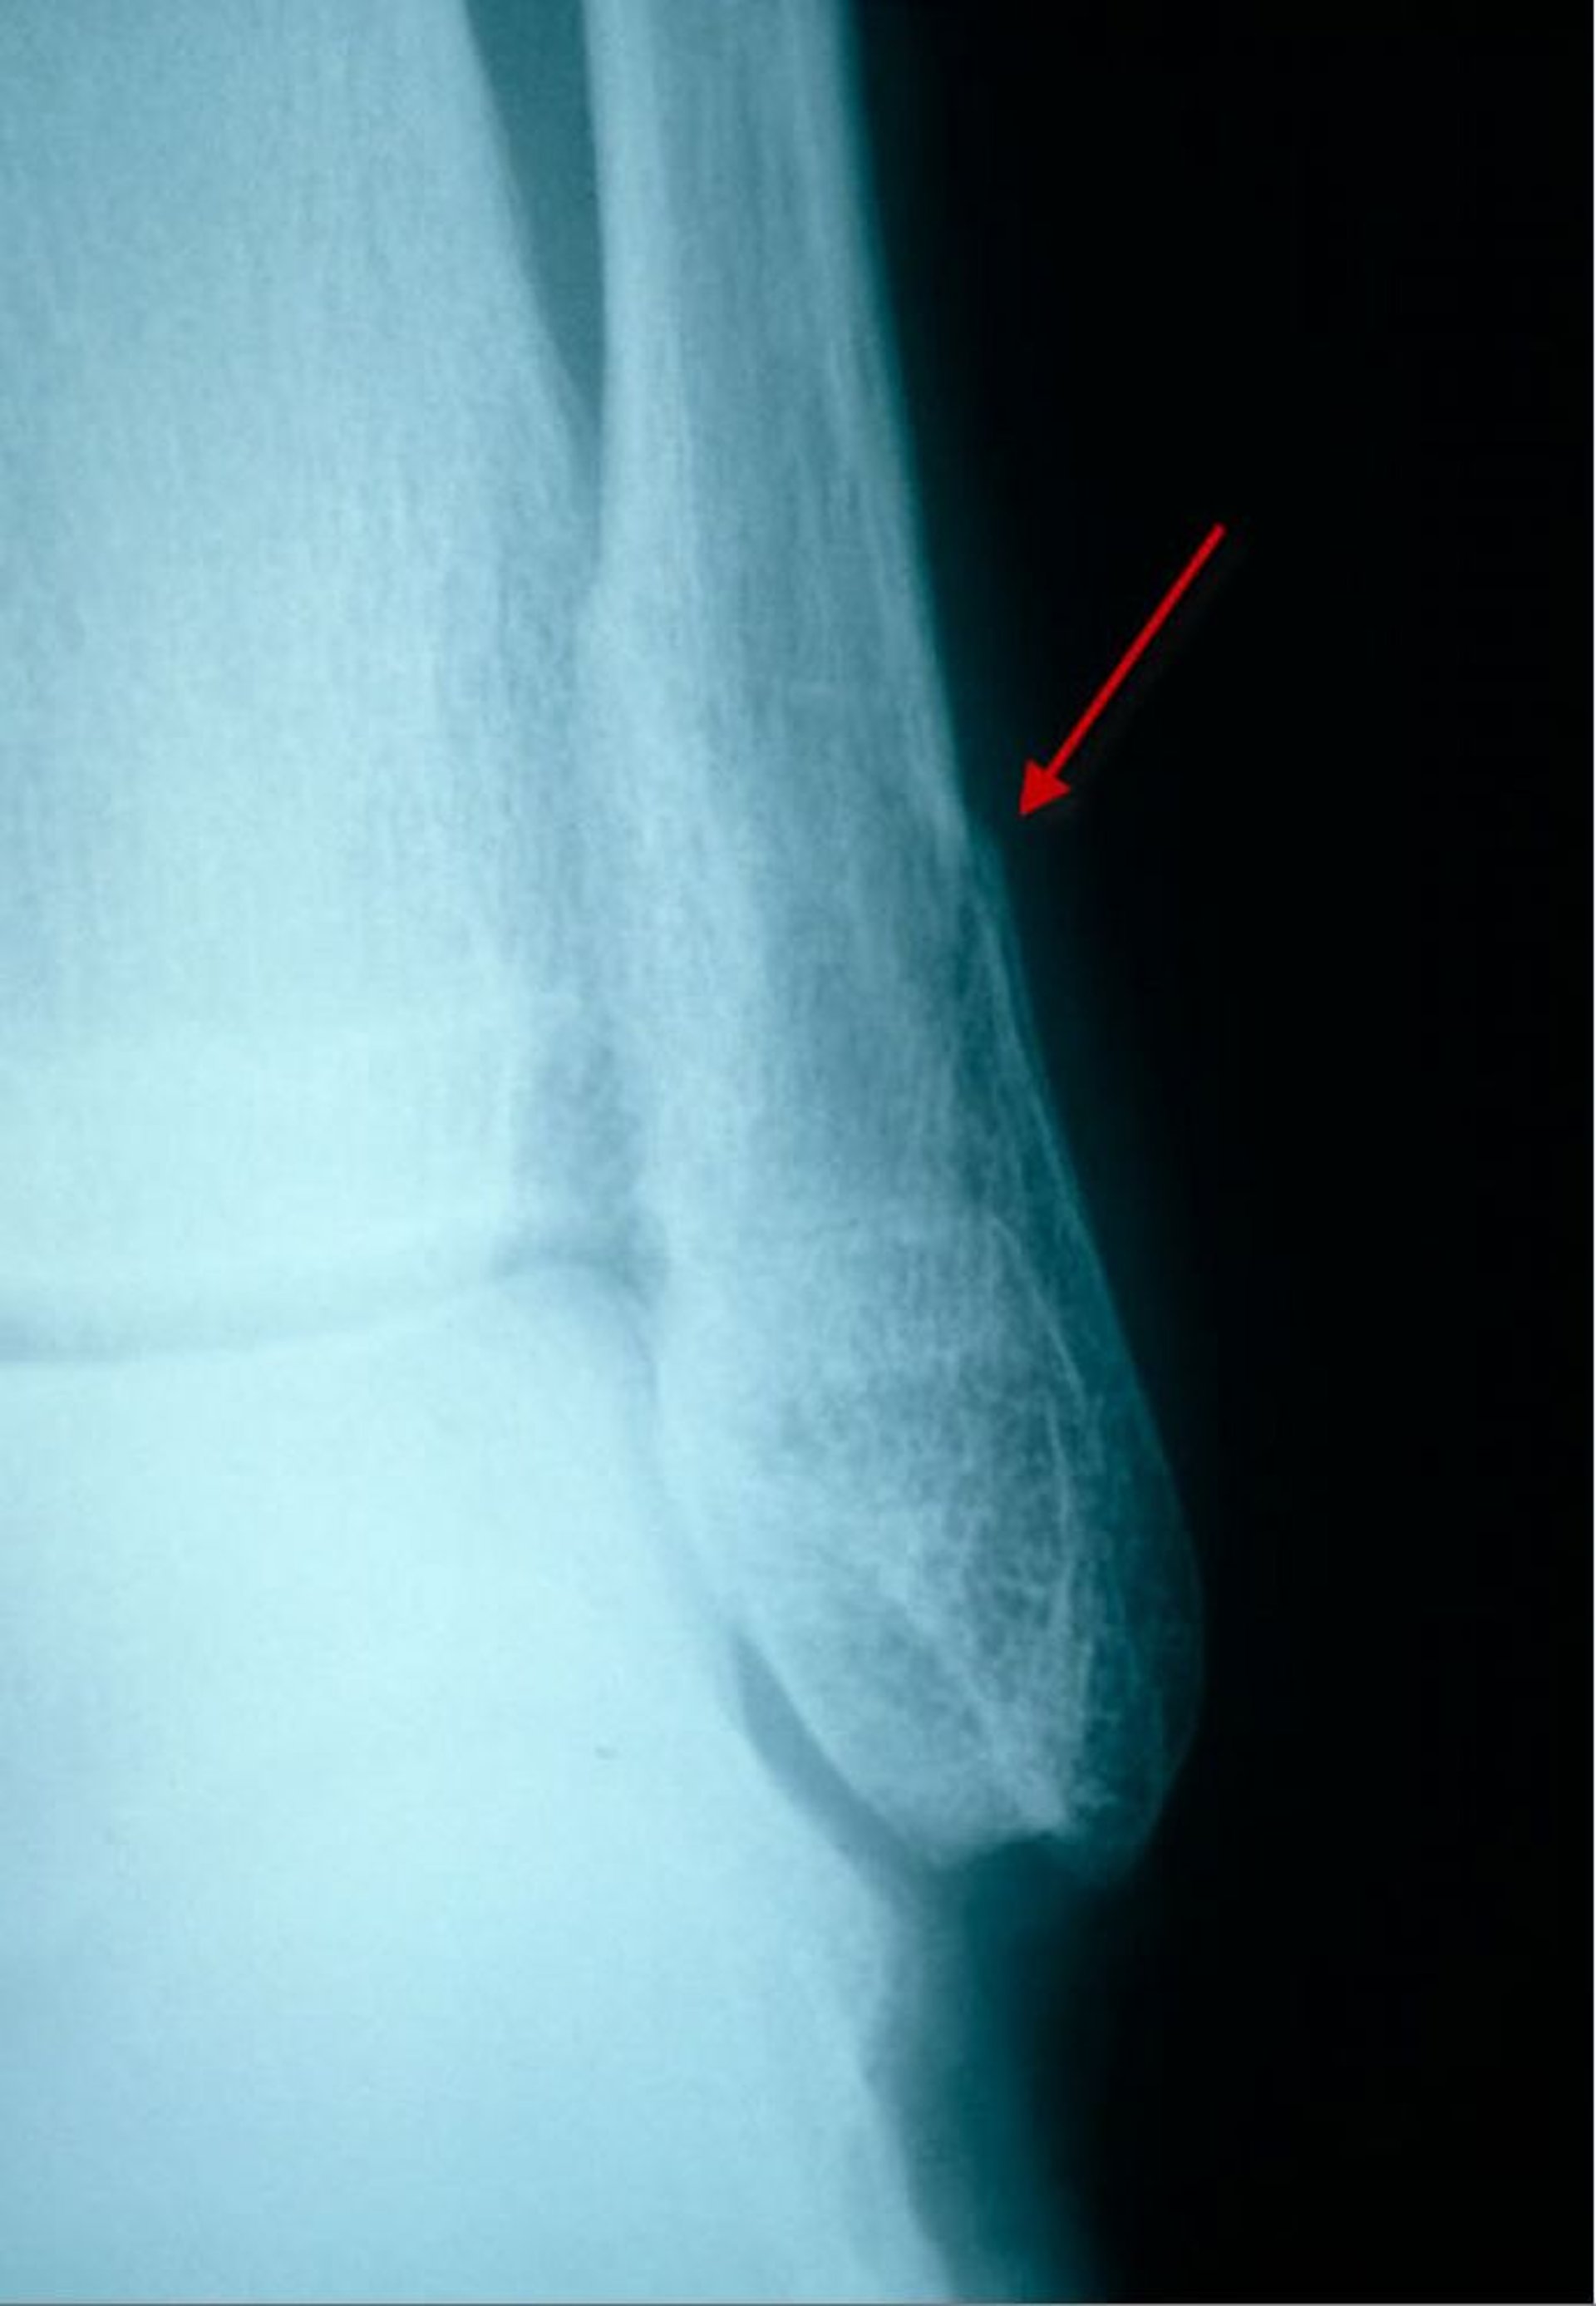

Fracture distale subtile du péroné (vue latérale)

Sur cette en incidence de profil, une fracture du péroné distal est visible comme une petite radiotransparence et une discontinuité (décalage) du cortex.